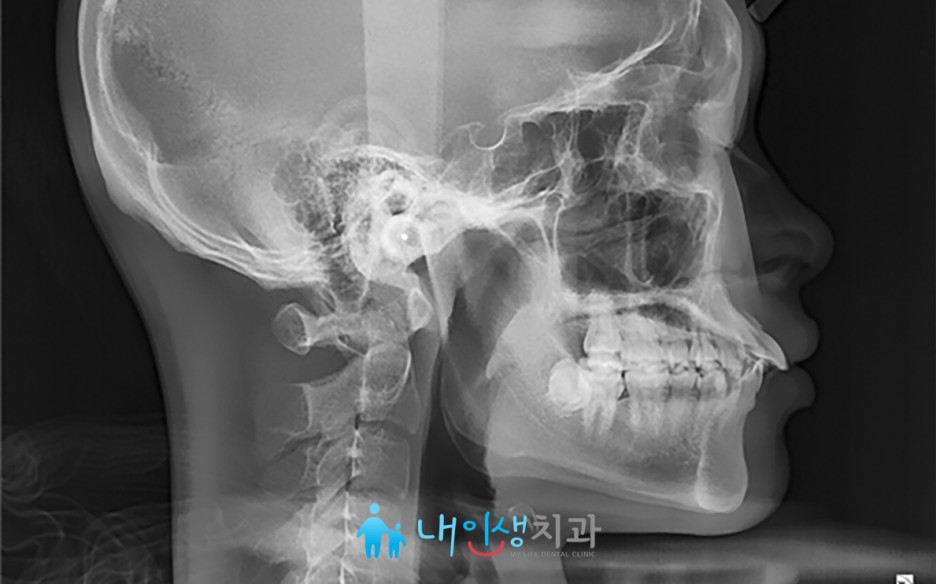

교정치료

내인생치과는 교정 전문의가 상주하여 다앙한 부정교합 케이스를 치료할 수 있습니다.

- 소아청소년교정 - 성장기 청소년에서 턱의 열성장이나 과성장을 성장 교정 장치로 미리 치료할 수 있습니다.

- 부분교정 - 치아가 상실된 채로 방치되어 치열이 무너졌거나, 어느 한 부위의 심미적인 문제를 부분 교정으로 해결할 수 있습니다.

- 중년교정 - 이제 교정 치료는 젊은 사람들만 할 수 있는 겻이 아닙니다. 삶의 질을 높이기 위해 나이와 상관없이 교정 치료는 필요합니다.

- 비수술교정 - 안면비대칭과 같은 질환에서 수술이 부담스러운 경우 교정적으로 해결할 수 있습니다.

서초치아교정 앞니 뻐드러짐 및 틀어짐 바로잡기 위한 치아교정 케이스

안녕하세요. 내인생치과입니다. ^^ 이번 포스팅에선 앞니 각도가 심하게 뻐드러져 있어 고민을 안고 내원해 주신 환자분의 사례에 대해 소개해 드리도록 하겠습니다. 치아가 심하게 틀어지면 위아래 교합이 제대로 맞지 않는 것은 물론 심미성도 떨어져 교정 치료로 개선하는 것이 좋은데요. 저희 병원을 찾아주신 환자분 역시 앞니 뻐드러짐이 심각해 고민을 안고 내원해…